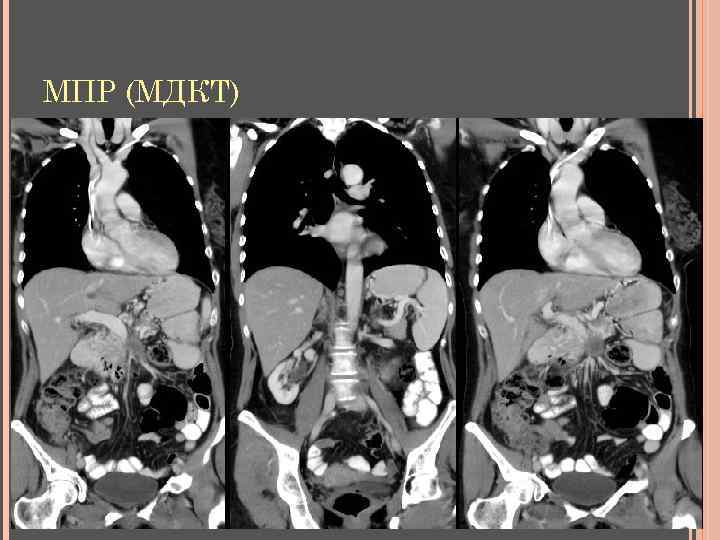

МПР (МДКТ)